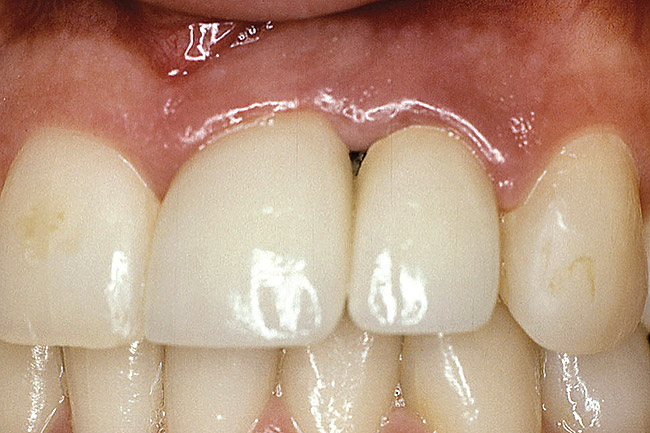

Figure 14  This patient exhibits ankylosed teeth Nos. 8, 9, and 10, but excellent bone.

Figure 14

Figure 15  Excellent bone levels.

Figure 15

Figure 16  Teeth Nos. 8, 9, and 10 were removed and immediate implants placed at the Nos. 8 and 10 sites.

Figure 16

Figure 17  Connective-tissue grafting in the pontic area of No. 9 and over the implant site No. 10.

Figure 17

Figure 18  Final restoration was achieved with a three-unit zirconia prosthesis: No. 8—implant abutment, No. 9—pontic, and No. 10—abutment.

Figure 18